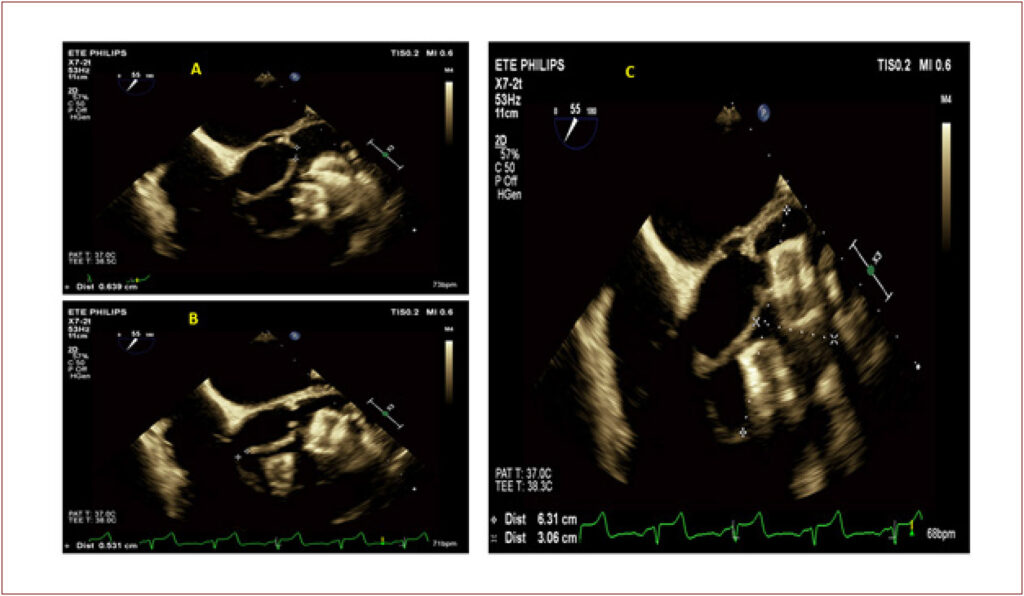

Ischemic Stroke in a Patient with Challenging Pseudoaneurysm in the Left Ventricular Outflow Tract

Literature shows cases of cardiac neocavities, often associated with pseudoaneurysms resulting from traumatic injuries or fistulized periprosthetic abscesses involving the left ventricle (LV).

Cardiac pseudoaneurysms are typically complications of acute myocardial infarction but can also occur in the late postoperative period of valve surgery. Certain areas are particularly prone to the development of ascending aortic pseudoaneurysms. Generally, these events occur in sites where aortic cannulation and clamping take place, as well as in the areas of graft sutures.